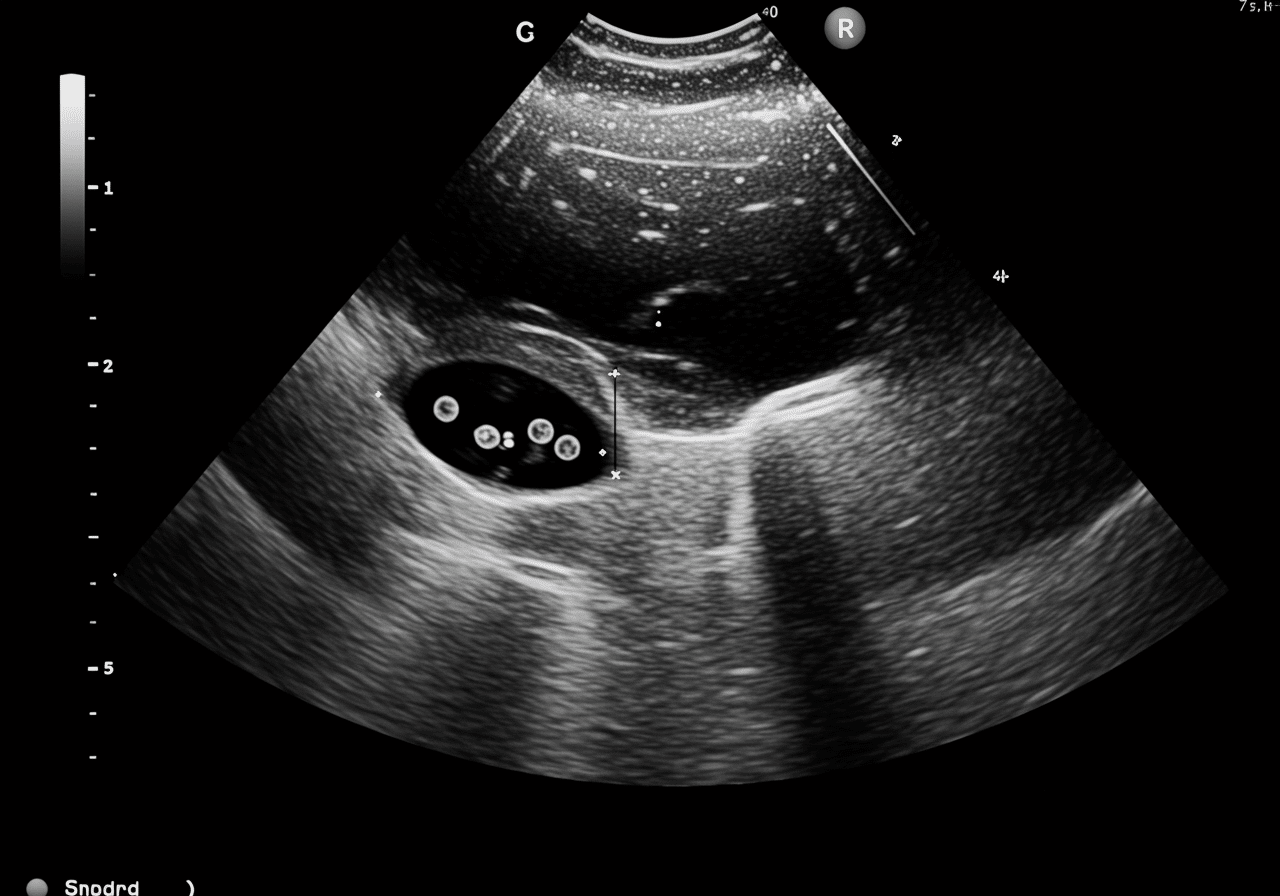

According to the American College of Emergency Physicians, the Focused Assessment with Sonography for Trauma (FAST) exam has revolutionized trauma care by detecting hemoperitoneum with 86-97% sensitivity in unstable patients, enabling immediate surgical decisions without CT delays that increase mortality[5]. The critical difference between survival and death in trauma often comes down to seeking appropriate ultrasound (FAST) for internal fluid, DVT evaluation, or gallbladder inflammation within minutes of injury for FAST exams, within 4 hours for DVT diagnosis preventing pulmonary embolism, and within 24-48 hours for acute cholecystitis preventing gangrenous gallbladder and sepsis[6]. Our trauma emergency capabilities include immediate bedside FAST examination evaluating Morrison’s pouch, splenorenal recess, pelvis, and pericardium, with positive findings triggering trauma activation and emergency laparotomy coordination.

Focused Assessment with Sonography for Trauma (FAST) is a bedside ultrasound examining four areas detecting free intra-abdominal or pericardial fluid indicating internal bleeding. Priority ER emergency physicians perform FAST immediately in trauma patients with hypotension, assessing Morrison's pouch (liver-kidney interface), splenorenal recess, pelvis, and pericardium within 5 minutes. Positive FAST with unstable vital signs indicates need for emergency laparotomy without CT delay, while negative FAST in stable patients allows CT for detailed injury assessment. FAST sensitivity reaches 86-97% in hypotensive patients but lower (63%) in stable patients requiring CT confirmation.